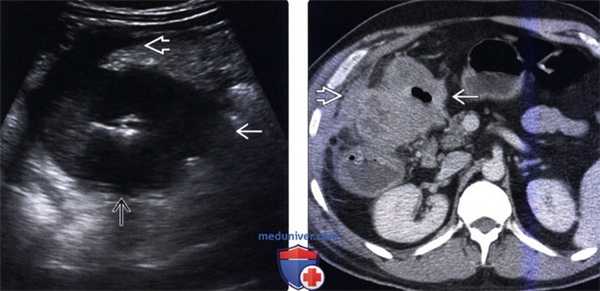

(Слева) На аксиальной КТ с контрастным усилением у мужчины 60 лет, страдающего раком правых отделов ободочной кишки с выявленными ранее метастазами в печень и анемией, визуализируется метастаз и киста, являющаяся случайной находкой.

(Справа) На аксиальной КТ с контрастом у этого же пациента определяется объемное образование восходящей ободочной кишки наряду с лимфаденопатией илеоцекальной брыжейки, что позволяет с большой степенью уверенности предположить лимфогенное метастазирование первичного рака толстой кишки. (Слева) На аксиальной КТ с контрастным усилением, выполненной мужчине среднего возраста с жалобами на неприятные ощущения в нижних отделах живота справа, визуализируются множественные вторичные узлы в сальнике.

(Справа) На КТ у этого же пациента определяется циркулярное новообразование в слепой кишке, обусловливающее обструкцию червеобразного отростка и прорастающее в окружающую жировую клетчатку. Рак слепой кишки может проявляться так же, как аппендицит—утолщением стенки кишки, инфильтрацией жировой клетчатки, растяжением просвета аппендикса. Наличие циркулярного образования в слепой кишке и метастазов в сальник или печень позволяет идентифицировать злокачественный процесс. (Слева) На аксиальной КТ с контрастным усилением у женщины 61 года с жалобами на запор и остро возникшую боль в животе и лихорадку, определяется дилатация толстой кишки с наличием в ее просвете жидкости и газа в сочетании с инфильтрацией расположенной поблизости жировой клетчатки.

(Справа) На более каудальном КТ срезе у этого же пациента определяется объемное образование сигмовидной кишки большого размера, обусловливающее кишечную обструкцию. Обратите внимание на асцит и инфильтрацию жировой ткани около толстой кишки. При оперативном вмешательстве подтвердился рак сигмовидной кишки, осложненный ишемическим колитом (нисходящей ободочной кишки).